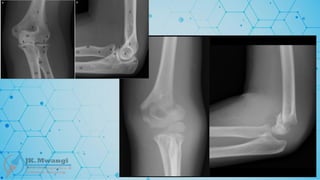

Monteggia fracture

 A fracture of the proximal third of the ulna with dislocation of the radial head.

Named after Giovanni Battista Monteggia in 1814